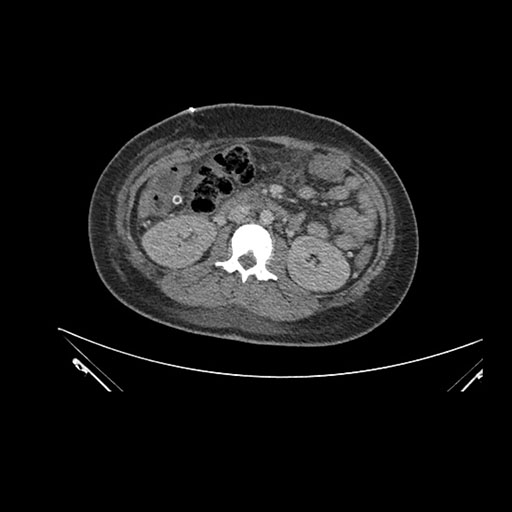

Imaging Analysis

Look through the patient's CT scan to identify any areas of concern for the necessary procedure.

Axial Arterial